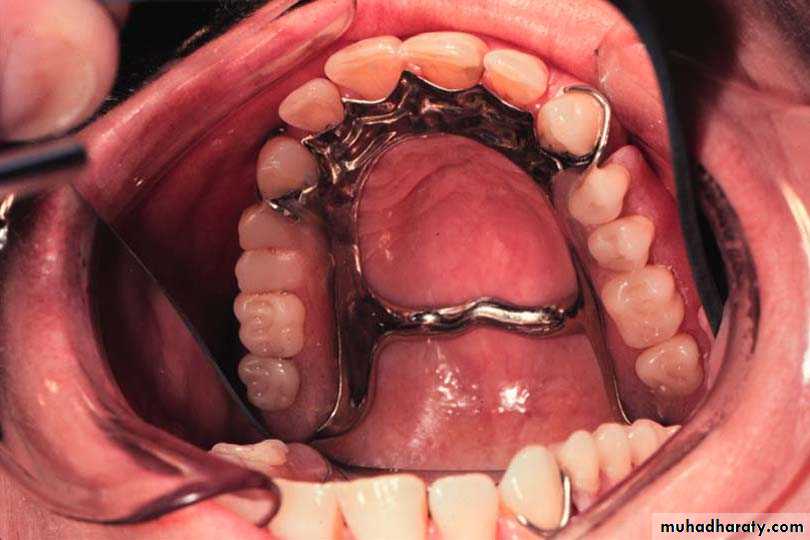

4-Combination anterior-posterior palatal strap

4-Anteroposrerior palatal strap(( closed horseshoe)) (cl I, II, III)

Design

1.The anterior strap should be positioned as back as possible on the rugae area.

2.The posterior strap should be placed as far back as possible on the hard palate.

3.The borders of the connectors should be placed 6 mm away from the gingival margins or should extend above the height of contour of the teeth

4-Relatively broad(8 to 10 mm) anterior and posterior palatal straps

5-Lateral palatal straps (7 to 9 mm) narrow and parallel to curve of arch.

6-Anterior palatal strap follows the valleys of the rugae at right angles to the median palatal suture.